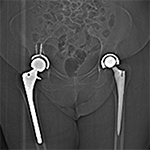

Figure 1 A Figure 1B Figure 2A Figure 2B

Streak artifact Streak artifact Hardware attenuation Hardware attenuation

Artifact Summation. (A) Scout image demonstrates bilateral total hip arthroplasties. (B) Axial CT image at the level of acetabular cup and femoral head shows severe transverse streaking related to total summed attenuation of metal components. Optimal Windowing. (A) Axial CT image of the pelvis viewed in soft tissue windows demonstrates extensive streak artifact due to total hip arthroplasty prohibiting evaluation of adjacent bone and soft tissue structure. (B) Same axial CT image set to bone windows results in improved visibility of adjacent bone and soft tissue anatomy.